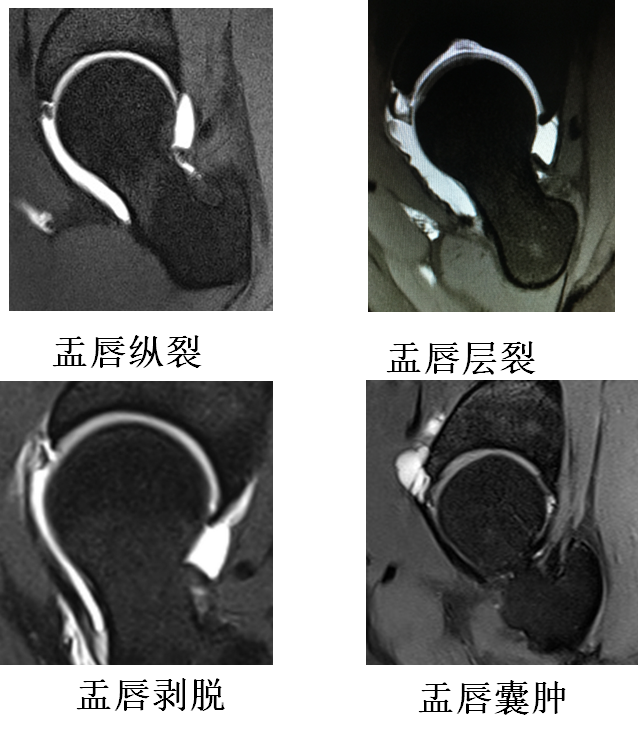

髋关节疼痛之髋臼唇撕裂影像学诊断

图片尺寸640x289

髋关节盂唇损伤和撞击症的mri检查指引 - 好大夫在线

图片尺寸1512x2137